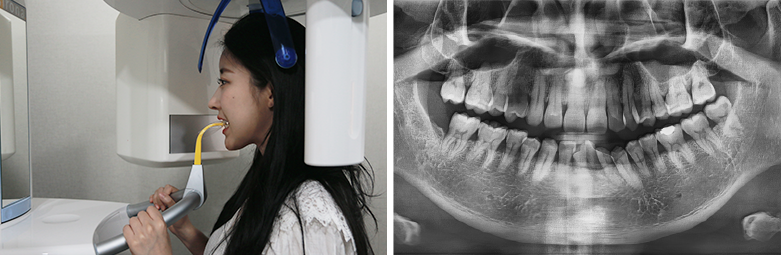

02

拍摄CT & X光片

Computed Tomography / Panorama

[ 拍摄CBCT ]

牙科CBCT拍摄是利用X线

3D视频重现牙槽骨和牙齿的硬组织 .

[ PANORAMA ]

确认整个牙齿的现状和

排列, 咬合, 颚关节状态 .

可确认牙槽骨吸收, 牙根炎症,

修复体的状态, 牙齿的状态等等 .